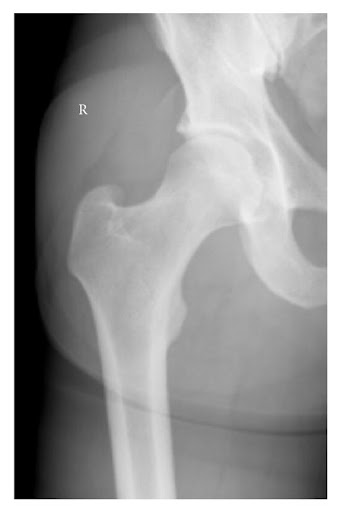

Chụp X-quang tại chỗ cho thấy khớp hông đã trở về đúng vị trí. Quá trình thực hiện thủ thuật không gặp khó khăn. X-quang được chụp một tuần sau thủ thuật cho thấy khớp háng phải đúng vị trí và không có dấu hiệu gãy xương (Hình 2). MRI được thực hiện một tuần sau đó cho thấy không có tràn dịch khớp háng phải nhưng có rách dây chằng tròn và tràn dịch khớp háng. Không thể phát hiện tổn thương sụn viền (Hình 3).

Chụp X quang khớp háng sau 1 tuần điều trị